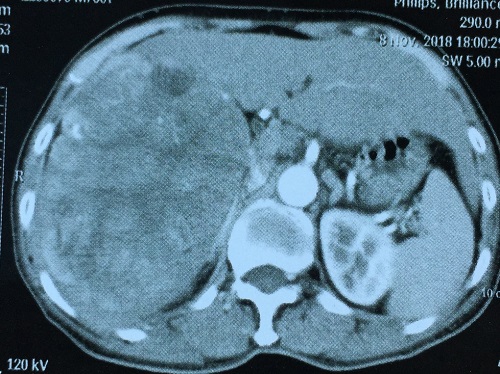

患者张某,64岁,因上腹部疼痛3天在当地医院就诊时行CT检查时发现肝右叶有一大小为14.2cm*10cm*13cm的肿块,考虑为肝癌可能性大。患者家属多方打听,决定来我院肝胆胰外科接受进一步治疗。入院后完善相关检查,临床诊断为右肝癌。患者家属考虑到肝脏肿块体积大,腹腔镜下难以完成,一度打算放弃腹腔镜下切肝。罗宏武教授团队的张辉主治医师,给患者家属分享大量的临床案例以及两种不同术式患者术后的恢复情况。充分沟通下,家属决定做腹腔镜下右半肝切除术。

术前罗宏武教授团队通过充分的术式预演,充分讨论了术中可能遇到的各种困难及解决方案,手术如期进行。罗宏武主任在张辉主治医师、涂彪住院医师的协助下,在手术空间不够的情况下,安全高质完成,手术历时4小时,将含巨大肿瘤在内的右半肝完整切除,术中失血量约为500毫升。术后患者感觉很轻松,自述像“没有做过手术一样”,按EARS进入快速康复程序,第二天就下床活动,并进食半流质。

据悉,腹腔镜下右半肝切除术,已是常规开展术式,但此患者右半肝肿瘤巨大,显露困难、手术空间小,手术难度非常高,转开腹可能性大。罗宏武教授团队在与患者和家属充分沟通后,勇攀手术技术高峰,使患者快速康复受益。